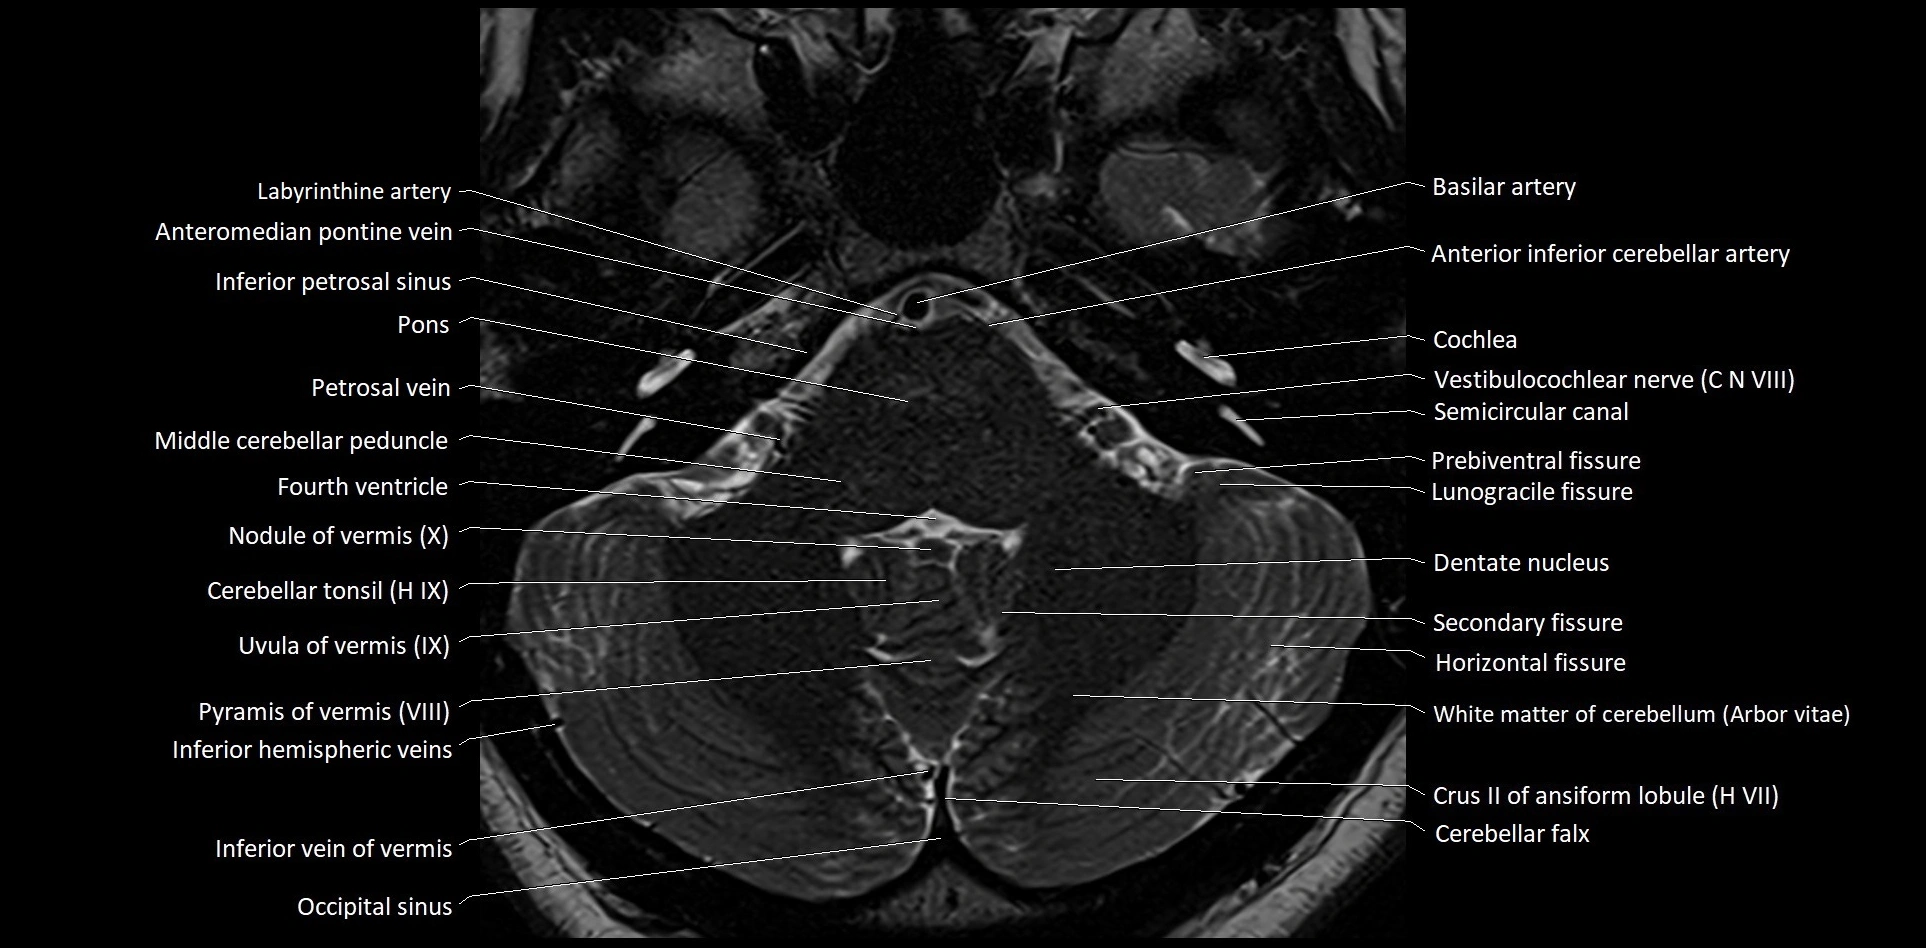

MRI images